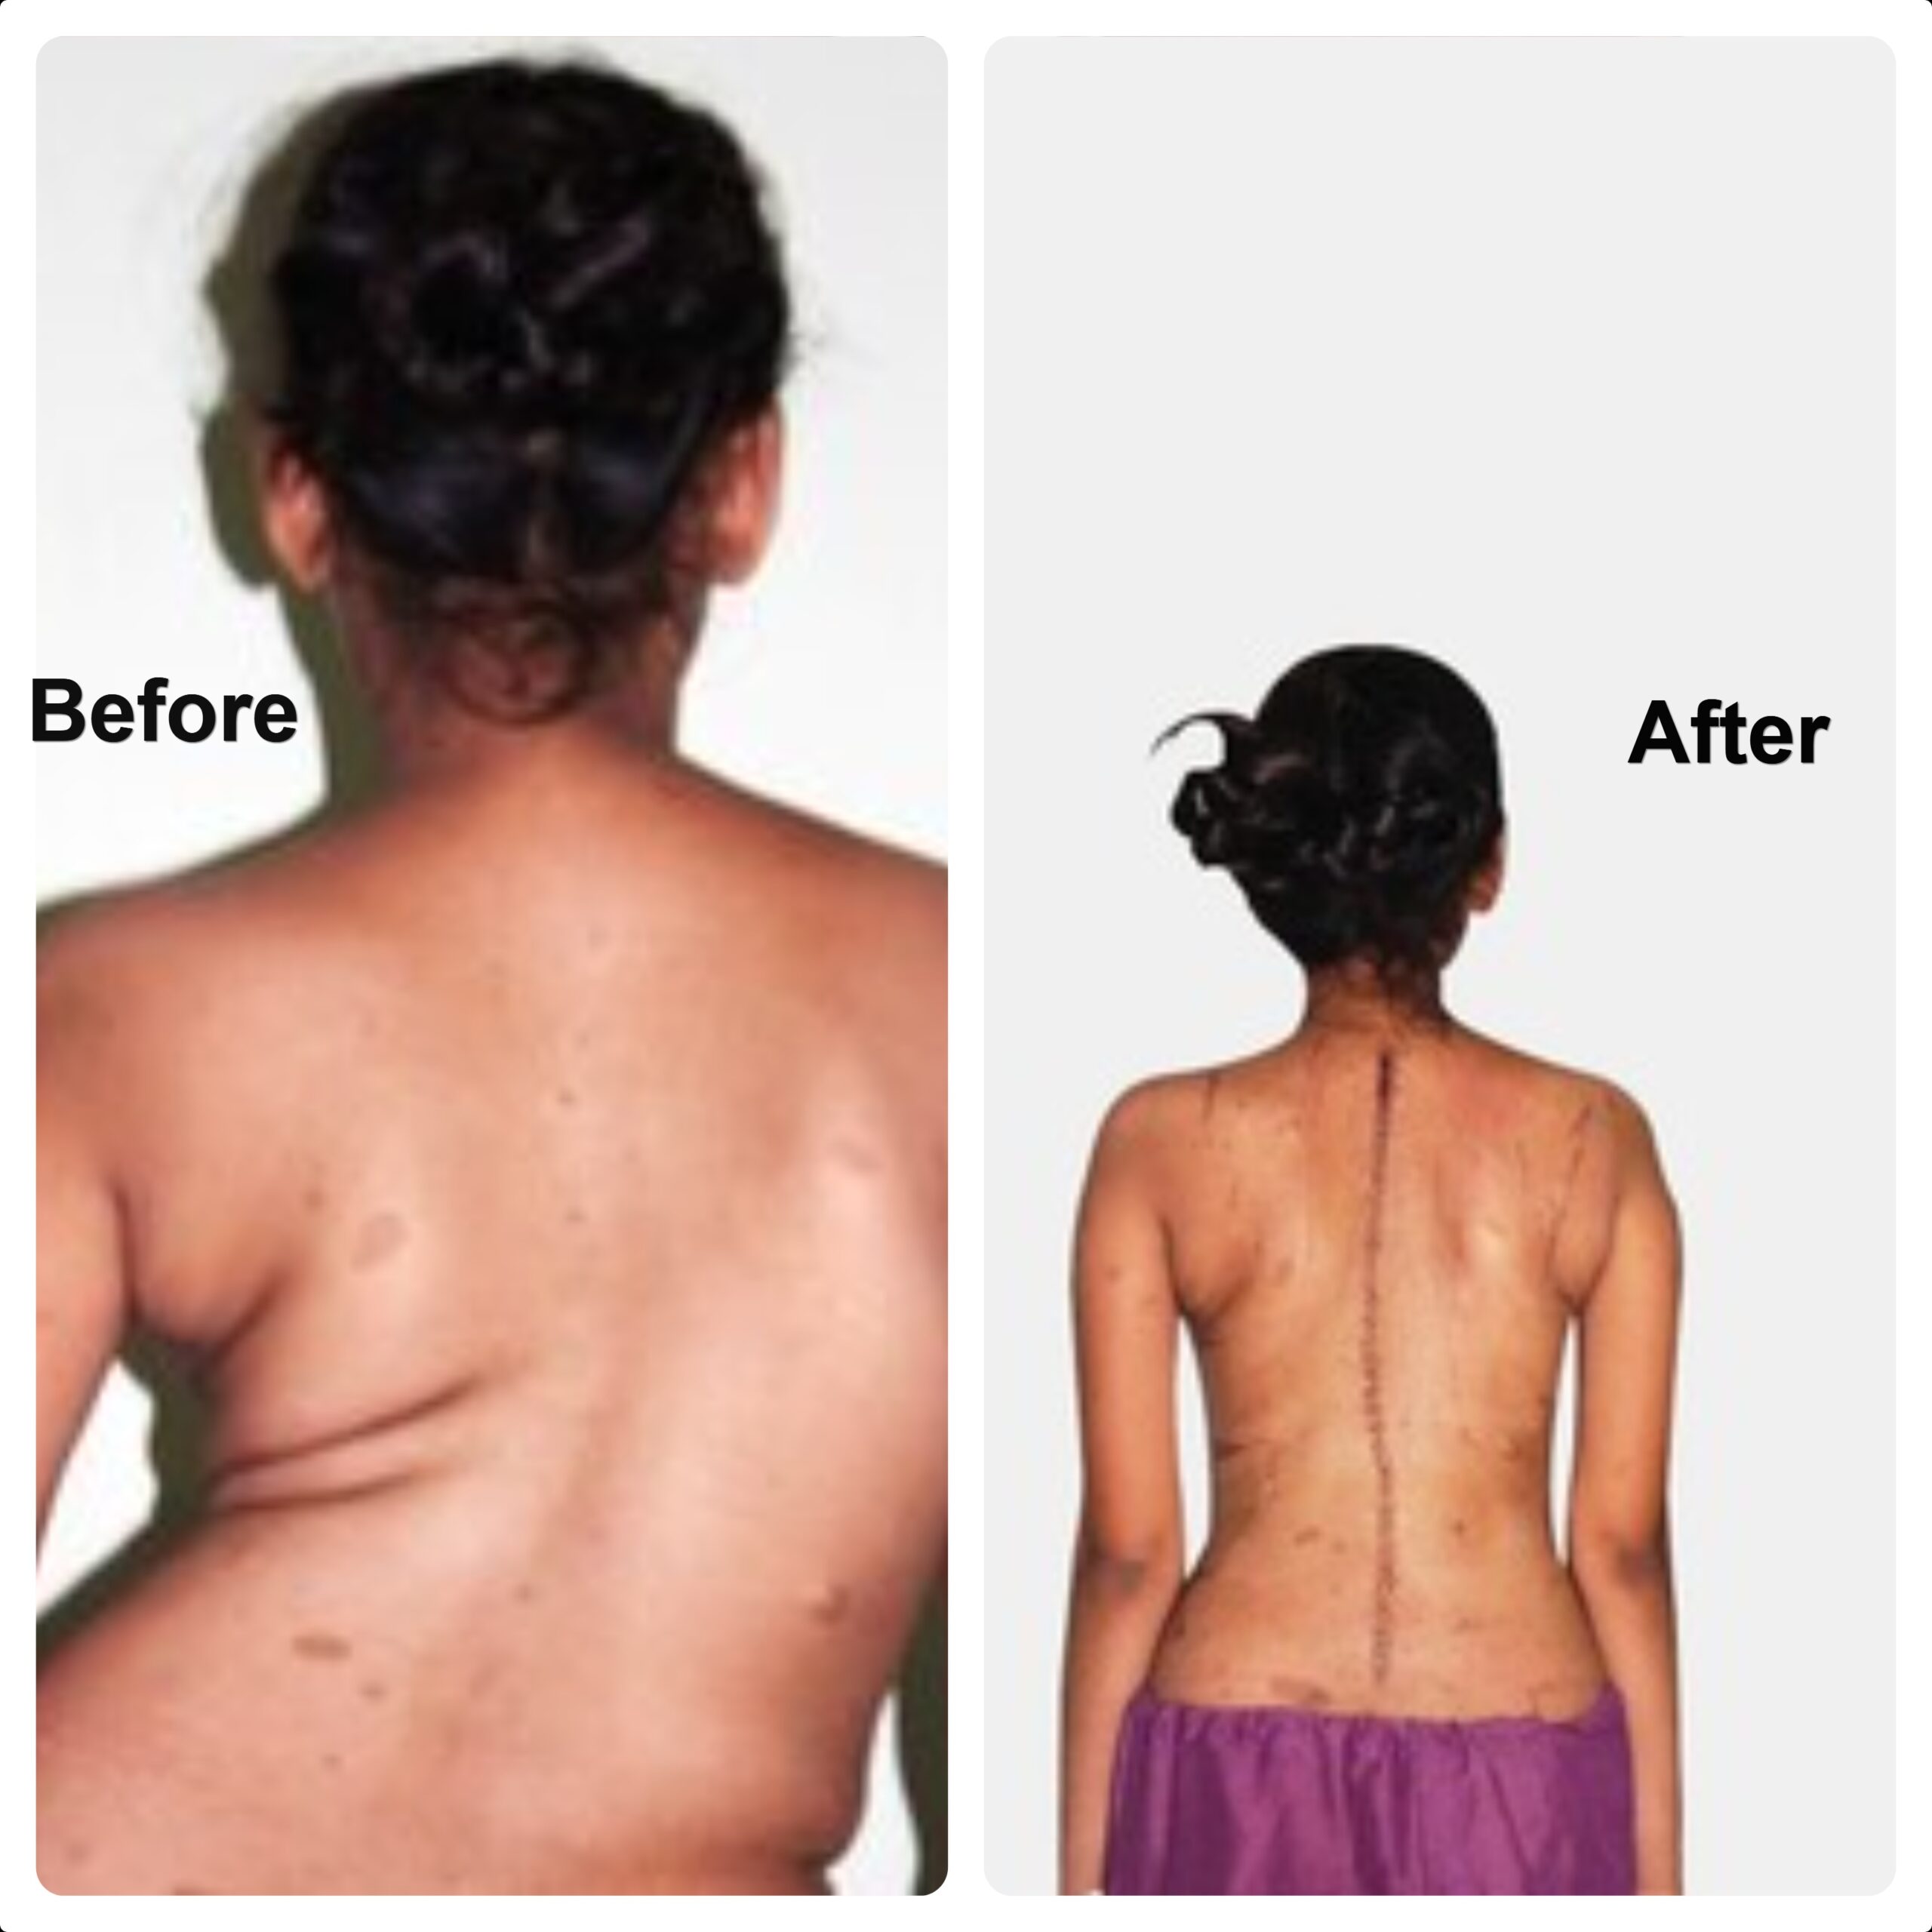

Scoliosis—Before and After Surgery